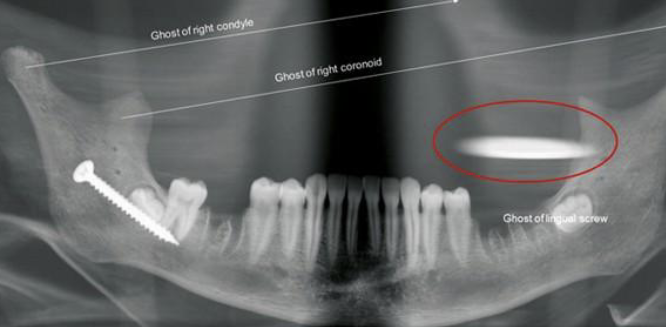

what is shown in the red circle

an artifact